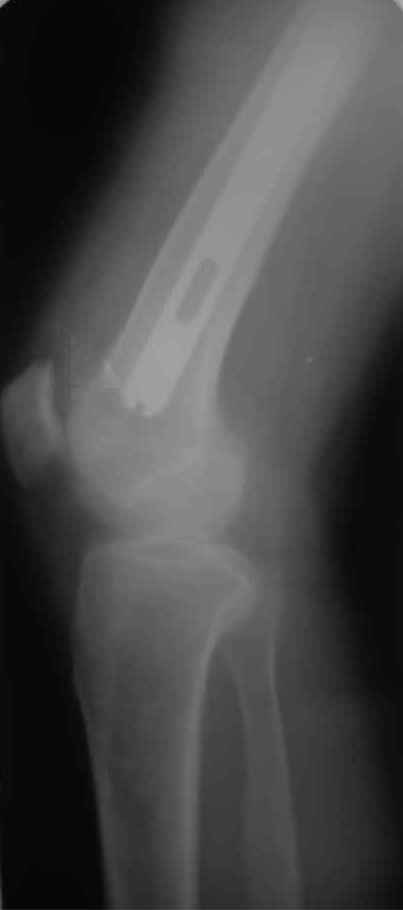

Произведено закрытое удлинение ножки эндопротеза с помощью ретроградного интрамедуллярного стержня. Продолжительность операции 3 часа. Два из них закрытое восстановление длины бедра диистрактором

таз-бедро.

А нельзя ли увидеть и профиль бедра на всем протяжении, т.е. и весь протез, и весь стержень? И фас бы с коленом.

новые снимки

Пациента удалось осмотреть недавно. Достигнутый результат сохраняется. Перелом бедра сросся. Конечность опорная и безболезненная, ходит без трости. Ножка, похоже, реинтегрировалась, как и надеялись. Снимки и фото в приложении. Комментарии приветствуются.

Надо ли что-то делать дальше, как полагаете? Убрать винты? Убрать "удлинитель ножки"? Или оставить все, как есть? Спасибо заранее.